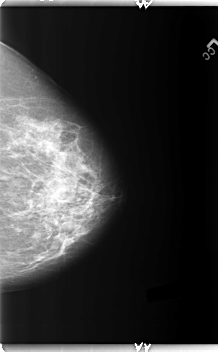

B_3148_1.LEFT_MLO

LEFT_CC LINES 5968 PIXELS_PER_LINE 3704 BITS_PER_PIXEL 12 RESOLUTION 50 NON_OVERLAY

LEFT_MLO LINES 5944 PIXELS_PER_LINE 3184 BITS_PER_PIXEL 12 RESOLUTION 50 NON_OVERLAY

FILE: B_3148_1.RIGHT_CC.OVERLAY

TOTAL_ABNORMALITIES 2

ABNORMALITY 1

LESION_TYPE CALCIFICATION TYPE AMORPHOUS-PLEOMORPHIC DISTRIBUTION CLUSTERED

ASSESSMENT 4

SUBTLETY 2

PATHOLOGY BENIGN

ABNORMALITY 2